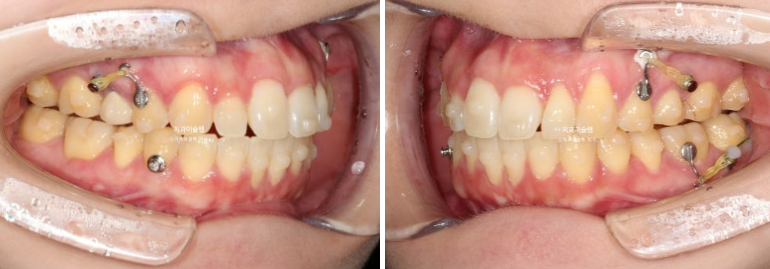

25년 5월부터 11월까지 20개 장치를 모두 낀 후 치료를 마무리 했습니다.

25.11

추가장치 이후 이제 중심선은 잘 맞습니다.

어금니 교합은 물샐틈 없는 1급 교합관계를 보입니다.

유지장치까지 들어간 모습입니다.